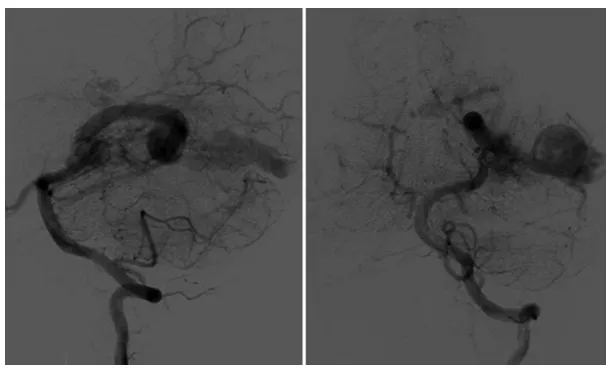

经过三次血管内治疗后,动静脉畸形的病灶体积显著缩小(图3)。整个治疗过程顺利,未发生任何并发症。

图3.第三次栓塞术后血管造影显示,动静脉畸形病灶显著缩小,仅残余少量由左侧大脑后动脉供血的残余部分。静脉动脉瘤仍然存在。